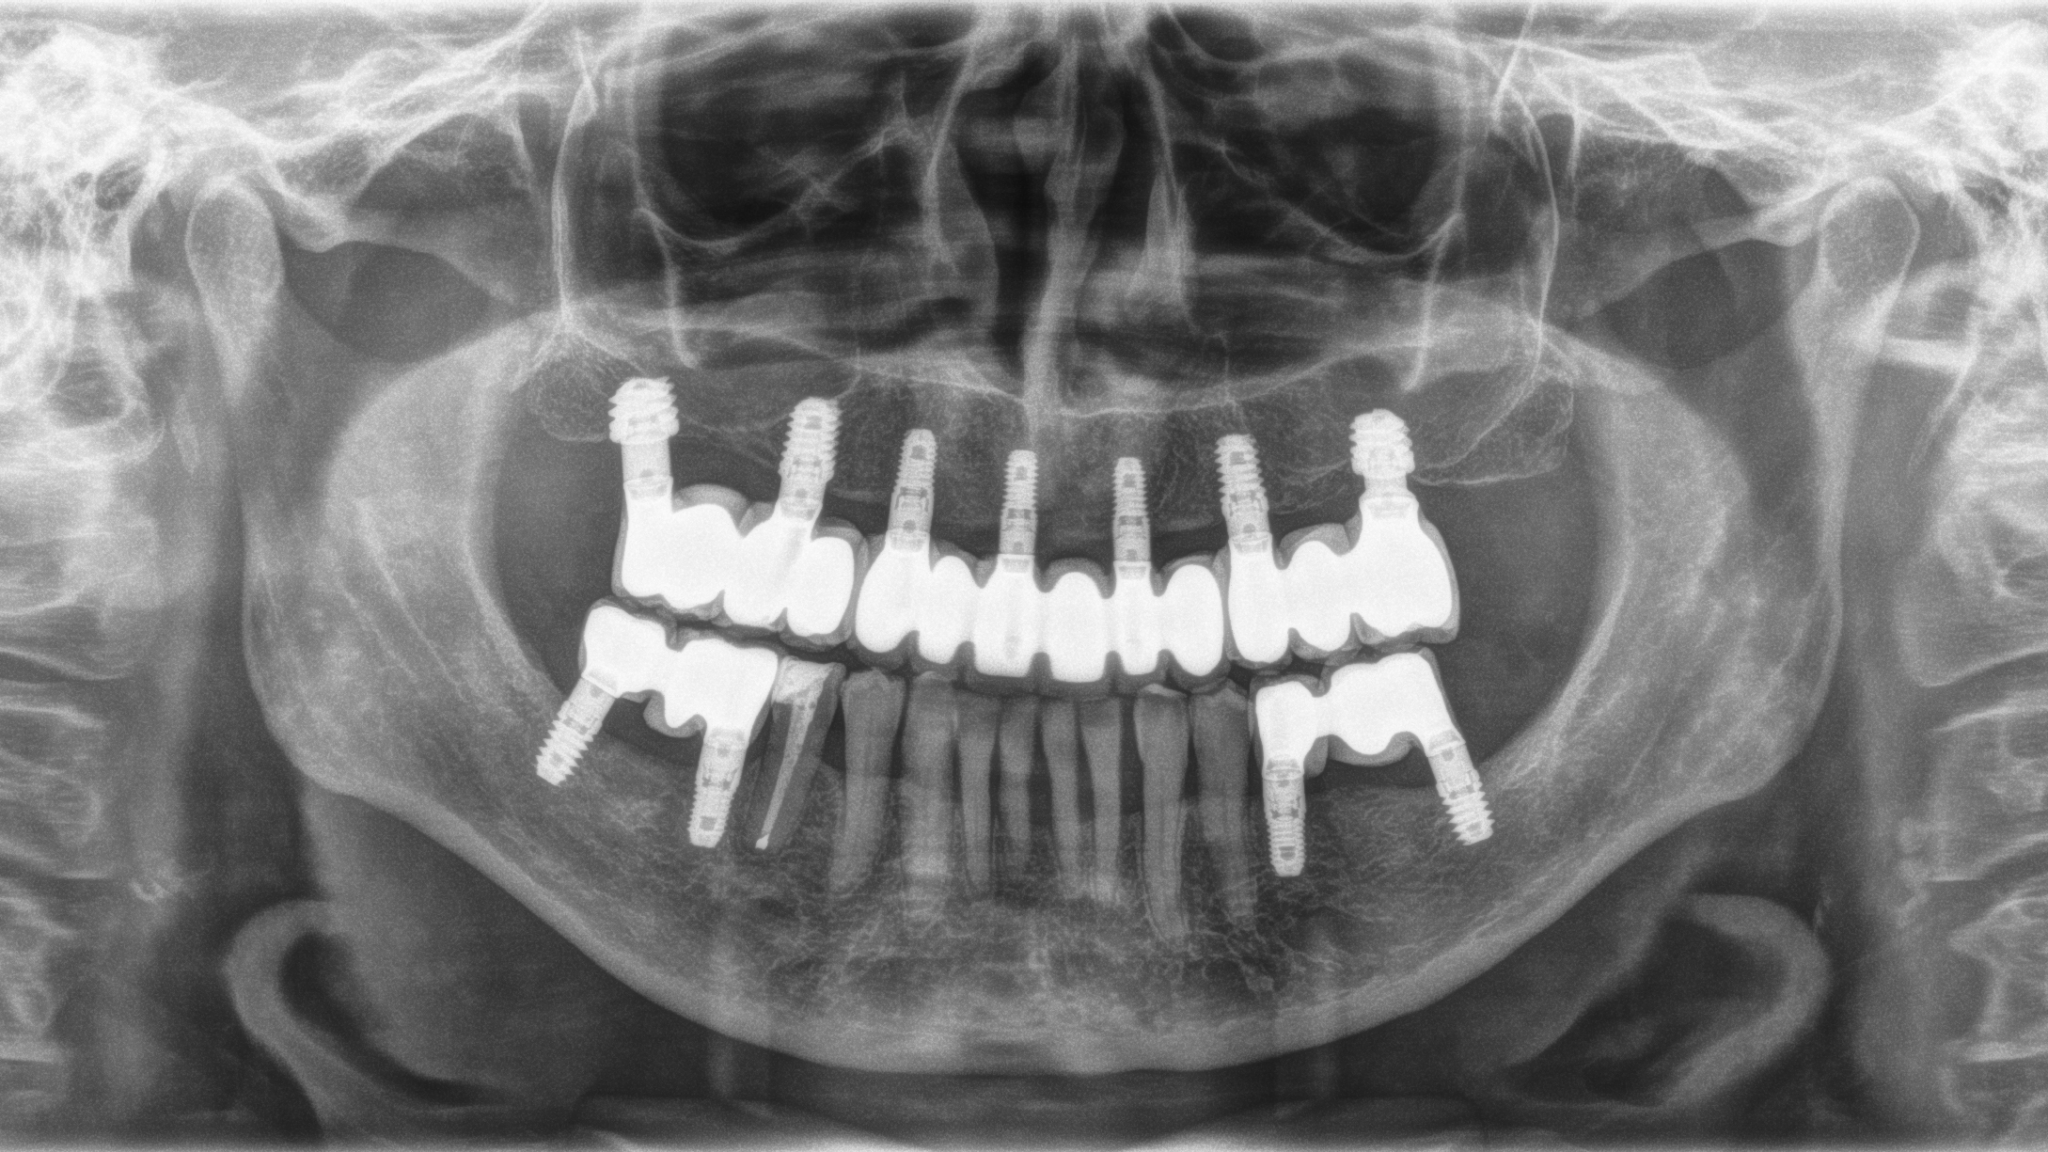

Transcrestal Sinus Lift Combined with Short Implants Inserted with Low Torque in Type IV and V Bone with 10 to 12 Years Follow-up.

Anitua_fig4 alternate text for this image

The transcrestal or transalveolar sinus lift procedure was described by Summers in 19941 as an alternative to the “traditional” approach, using the lateral window to reduce the morbidity of the technique. As initially described, the procedure consisted of an approach from the alveolar ridge using progressive caliber osteotomes that are activated using a hammer that … Read more